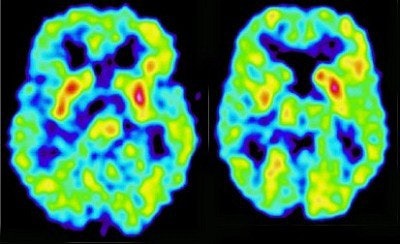

In another smaller study, her group used PET to study the cerebral glucose metabolism of 19 HIV-positive men who presented with MMD. Five had undetectable virus levels, and the rest had viral loads ranging from less than 1,000 to 30,000 copies of viral RNA per milliliter of blood.

"In patients responding to HAART (highly active antiretroviral therapy), we found an up-regulation of metabolism in the basal ganglia," Arendt said, while those who were either not on therapy, or failing therapy, showed a lowering of metabolism in the same region.

| PET scan of an HIV-1 positive patient with decline of PET activity in the right basal ganglia (right side of the image). Image courtesy of Dr. Gabriele Arendt. |

Interestingly from a therapeutic point of view, the up-regulation appears to be an artifact of the viral attack; if the patients responded well to therapy, the metabolism returned to normal, she said.

"If the virus is stopped, the patient normalizes, the PET normalizes, the metabolism normalizes," Arendt said. "You know in which patients HAART is helping in the brain and in which it isn’t doing anything." This makes PET scanning a potentially useful tool for HIV-positive patients who seem to be responding to treatment based on conventional tests.